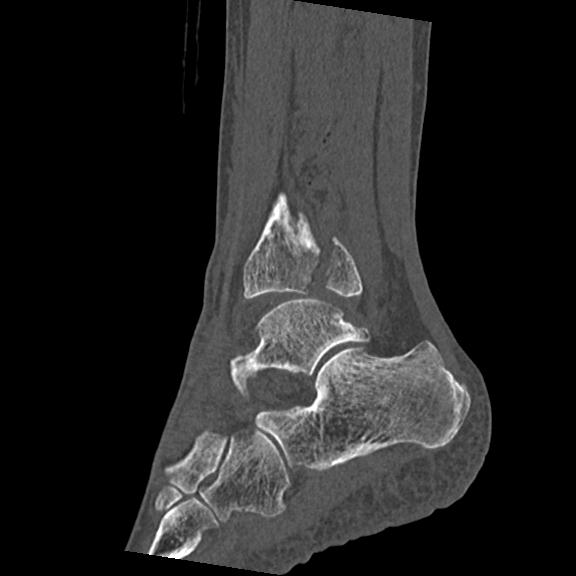

56476 8/28 4R 1/21 2R 左足関節 デジカメ写真 72歳女性 右足関節AS

102755 1/4 2R 1/15 2R 右足関節 68歳女性 右三果脱臼骨折